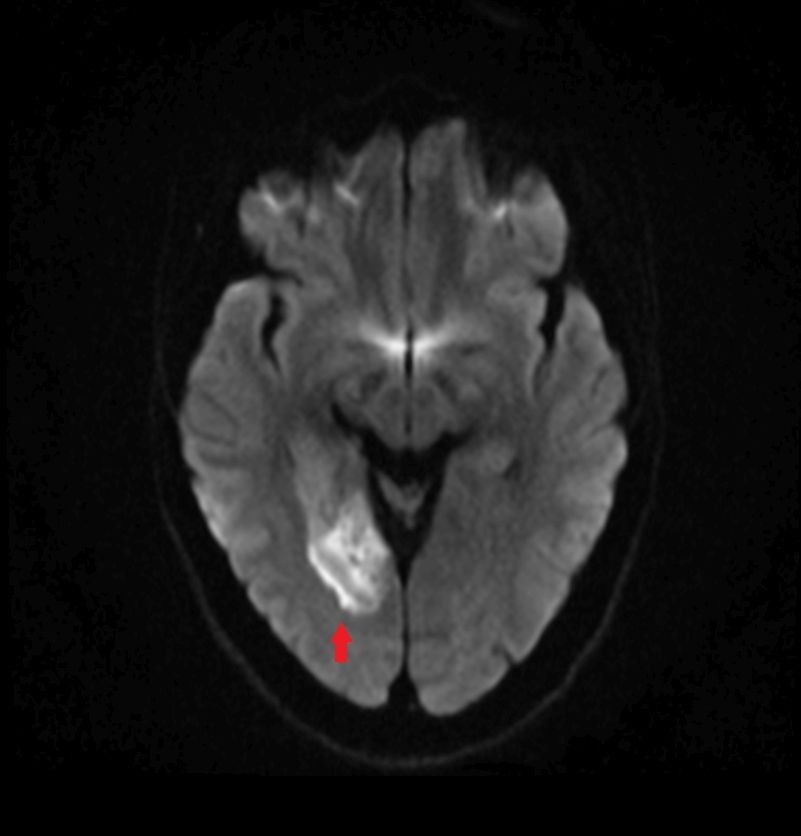

diffusionsgewichetes Bild bei Infarkt

gleicher Patient mit ADC-Karte